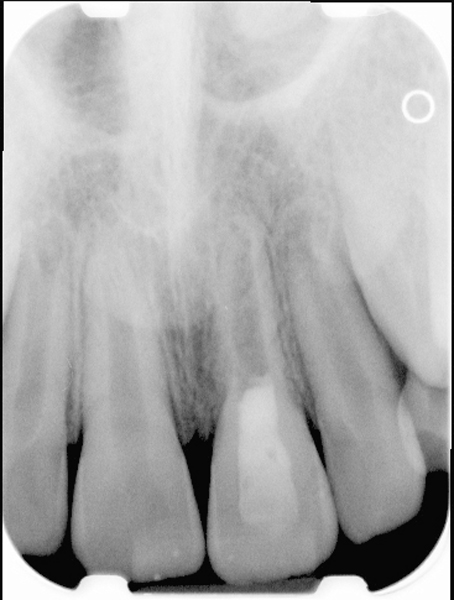

Fig 9 Preoperative radiographs showing mesial perforation.

Figure 9

Fig 10. Preoperative radiographs showing mesial perforation.

Figure 10

Fig 11. MTA perforation repair done, and calcium hydroxide medication placed in the canals.

Figure 11

Fig 12. Postoperative radiograph.

Figure 12

Fig 13. 2-year follow-up radiographs showing the positive outcome.

Figure 13

Fig 14. 2-year follow-up radiographs showing the positive outcome.

Figure 14